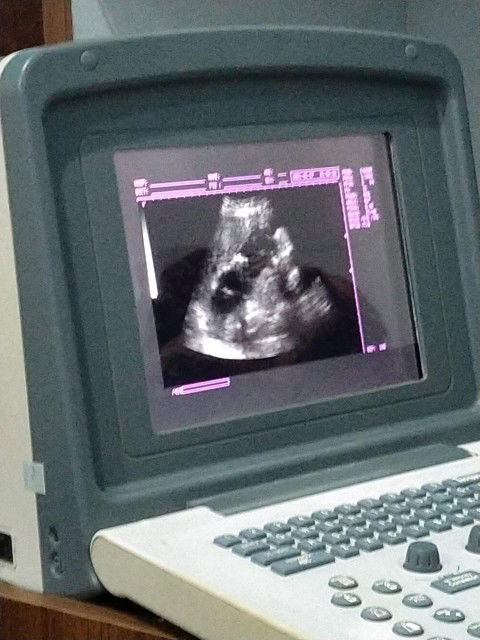

asih mmengandung bun

hamil pertama

belum melahirkan

blm lahir bun

blom lahiran